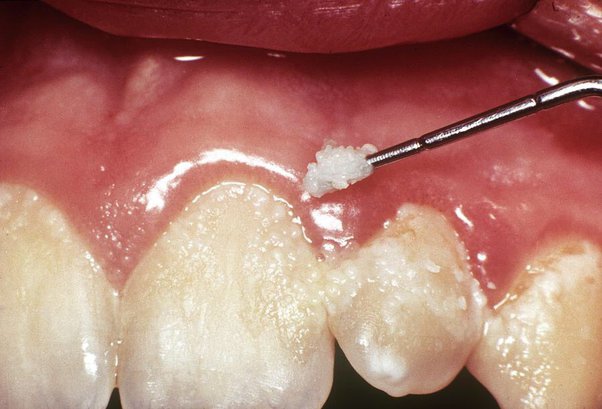

- However, sucrose has the unique property in that it is the main dietary substrate involved in the synthesis of soluble and insoluble extracellular glucan by glucosyltransferases (GTFs) from S. mutans. There are several mechanisms to explain the role of extracellular glucans as the major caries- associated microbial virulence factor. There is evidence that their presence in plaque promotes bacterial adherence to the tooth surface and contributes to the structural integrity of dental biofilms. Studies using an in situ caries model have shown that the presence of insoluble glucan markedly enhanced demineralisation potential of S. mutans test plaques. The effect has been attributed to an alteration of the diffusion properties of plaque, allowing deeper penetration of dietary carbohydrates.